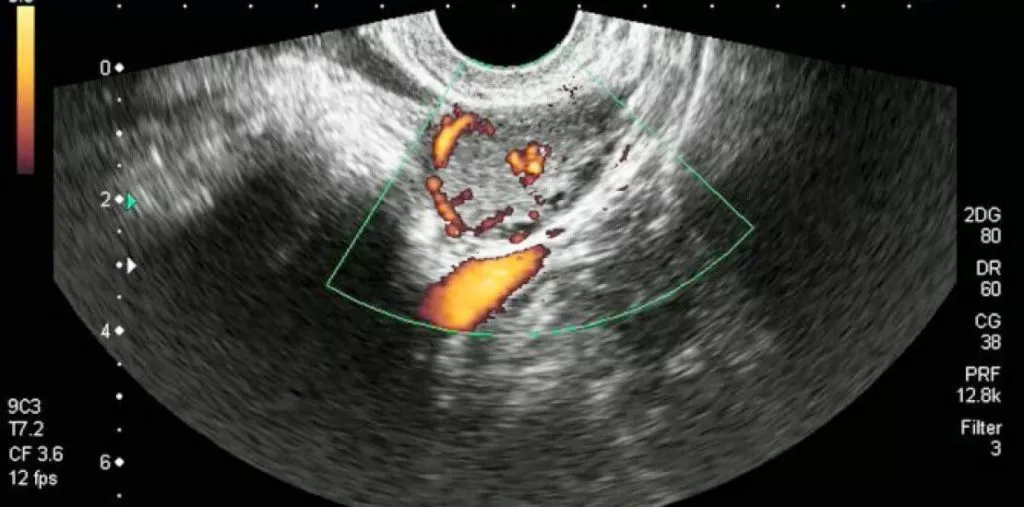

- УЗД яєчників — для візуальної оцінки формування та розвитку

Сучасні методи діагностики дозволяють точно оцінити стан жовтого тіла. УЗД з доплером допомагає оцінити кровоток у жовтому тілі, що важливо для визначення його функціональної активності. Аналіз на прогестерон найбільш інформативний, якщо його здати в середині лютеїнової фази — приблизно на 7 день після овуляції.